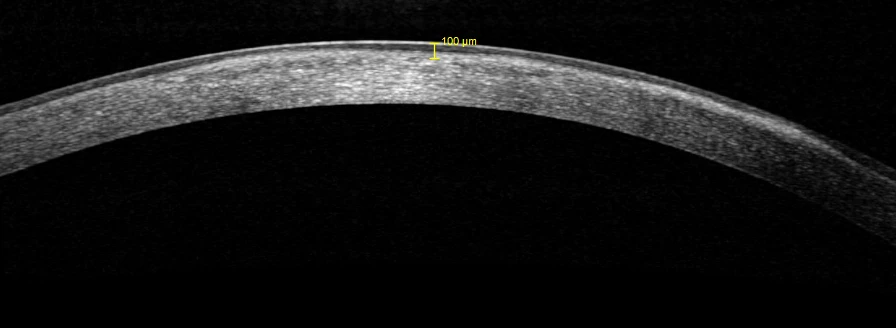

Left eye OCT shown below.

Bilateral Granular dystrophy type 1 (with recurrent corneal epithelial erosions in the left eye)

This girl has Granular dystrophy type 1, which is an autosomal dominant condition affecting the TGFB1 gene. She had associated recurrent erosion of the corneal epithelium. Trans epithelial PTK was performed, ablating a combined 100 microns of tissue (approximately 50 microns of epithelium and 50 microns of stroma). Two months after the procedure, the left VA was 6/9 with no pain. Ablation to a depth that eliminates all of the lesions is not recommended as this removes too much tissue. Repeat ablation would be considered in the future, should the VA fall again and eventually an anterior lamellar transplant will probably be needed.